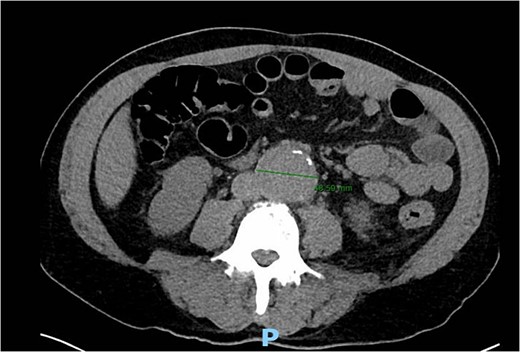

A 56-year-old male with no reported past medical history and a 70 pack year smoking history presented with a chief complaint of lower abdominal pain and body aches. On presentation, the patients white blood cell count (WBC) was 39.6 and procalcitonin was 43.4. Blood cultures were drawn and demonstrated P. mirabilis bacteremia. Computed tomography (CT) abdomen/pelvis was performed as well as ultrasound (US) of scrotum demonstrating a complex fluid collection within scrotal sac that was determined to be a scrotal wall abscess. The patient was started on a course of Unasyn and Urology promptly took him to the operating room (OR) for incision and drainage. Vascular surgery was consulted due to an incidental finding of an abdominal aortic aneurysm on CT measuring 4.7 × 4.6 cm (Figs 1 and 2). The patient was evaluated by the vascular surgery team following his urological procedure and denied any history of abdominal pain or back pain. Physical exam was largely unremarkable however the patient’s bilateral toes were noted to have blue discoloration with motor and sensation intact. Outpatient follow up with routine US scans for the AAA was recommended. Ankle brachial index (ABI) as well as an echocardiography was ordered to further work up the patient’s dusky toes. On Day 2 of hospitalization, ABIs returned showing severe peripheral vascular disease (PVD) and the echocardiography ruled out endocarditis. At this time an angiogram was planned to further the patient’s PVD workup however this was deferred as the patient remained septic with a WBC of 30. Over the course of the next few days the patient refused antibiotics and remained septic with a WBC in the 20s. At this time his toes quickly deteriorated from dusky to dry gangrene. On Day 8 of hospitalization the patient remained septic and was now complaining of new onset mid-abdominal pain. Emergent CT showed AAA was now 7.7 × 7.8 cm with periaortic fat stranding concerning for impending rupture (Figs 3 and 4). The patient was taken emergently to the OR for open repair. Upon visualization, the abdominal aortic aneurysm was clearly infected with signs of impending rupture on the left lateral wall and purulent material including infected thrombus. Tissue was cultured however showed no growth, likely due to the fact that the patient had been on antibiotic therapy for a week at this time. Reconstruction with an aorto-biiliac bypass using rifampin-soaked dacron graft was performed. A piece of omentum was mobilized over the graft and the retroperitoneum was closed over it. The abdomen was left open for a return to the OR for a second look which showed no concerns for bowel ischemia, worsening infection or bleeding. On post-op Day 5 the patient was extubated, off pressor support, and transferred to the floor. The patient’s postoperative course was unremarkable except for bilateral toes demarcating to dry gangrene.

Frontal CT angiography of the abdomen and pelvis demonstrating 7.75 cm AAA with fat stranding.

Axial CT angiography of the abdomen and pelvis demonstrating 7.7 cm AAA with fat stranding.